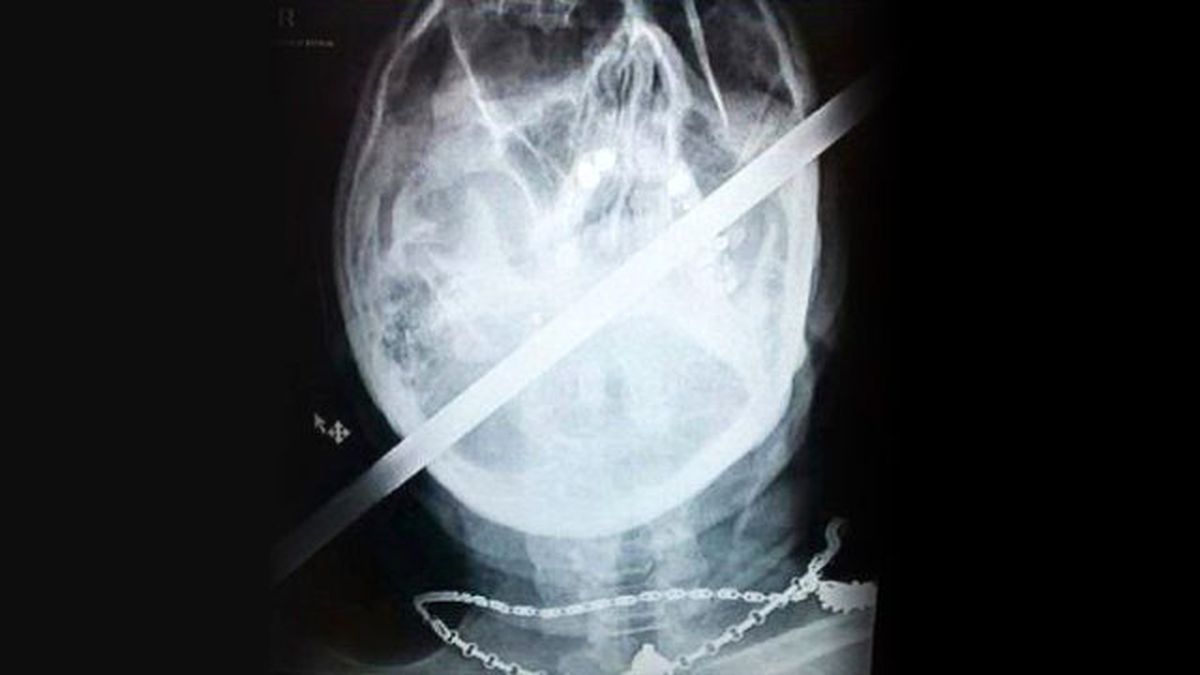

İngiltere'de bisikletiyle şarampole yuvarlanaran deneyimli bisikletçi Paul Bradshaw'ın kafasına yaklaşık 120 santimetre uzunluğunda demir bir çubuk saplandı.

İngiltere'de yaşayan deneyimli bisikletçi Paul Bradshaw, arkadaşlarıyla gezerken korkunç bir kaza yaptı. Bisikletiyle şarampole yuvarlanan Bradshaw'ın kafasına yaklaşık 120 santimetre uzunluğunda demir bir çubuk saplandı.

İngiliz The Sun gazetesinin haberine göre; Bradshaw, mucizevi bir şekilde iyileşerek, kazadan sadece iki gün sonra hastaneden taburcu oldu. Doktorlar, Bradshaw'un iyileşmesi karşısında şaşkına döndü. "Şarampole yuvarlandığımda, orada çelik güçlendirme çubuğu vardı. Sağ omzumdan geldi ve ensemden saplanarak ağzımın sol tarafından çıktı." diyen Bradshaw, 4.5 saatlik ameliyatın ardından kendine geldi. Ancak talihsiz İngiliz, kaza sonrası başından geçen neredeyse hiçbir şeyi hatırlamıyor.